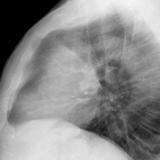

Case 8b Thymoma Lat

Date: 03/27/2009

Views: 14089